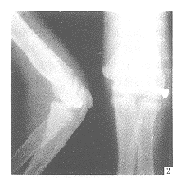

肘关节侧方脱位3例

Three cases of lateral dislocation of elbow